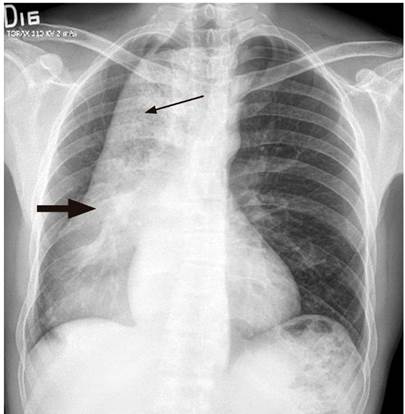

Hombre de 42 años, conductor, sin antecedentes de importancia, quien consultó por un cuadro de 3 años de evolución de disfagia progresiva inicialmente para sólidos y luego para líquidos, y regurgitación; con un aumento de los síntomas en los últimos 4 meses, se asocia con pérdida de 15 kg de peso (Eckardt 9). Al ingreso tenía signos de desnutrición grave y halitosis, sin disnea, adenomegalias periféricas, visceromegalias o ascitis. Se pasó una sonda nasogástrica y se obtuvo un drenaje alimentario abundante. Se realizó una radiografía de tórax en la que se registró una aparente masa mediastinal que desplaza la línea media (Figura 1). Ante este hallazgo y tos seca persistente, se complementa con una tomografía axial computarizada (TAC) de tórax con contraste, en la que se reportó megaesófago y hallazgos sugestivos de acalasia, sin poder descartar un compromiso neoplásico en la unión gastroesofágica (Figura 2).